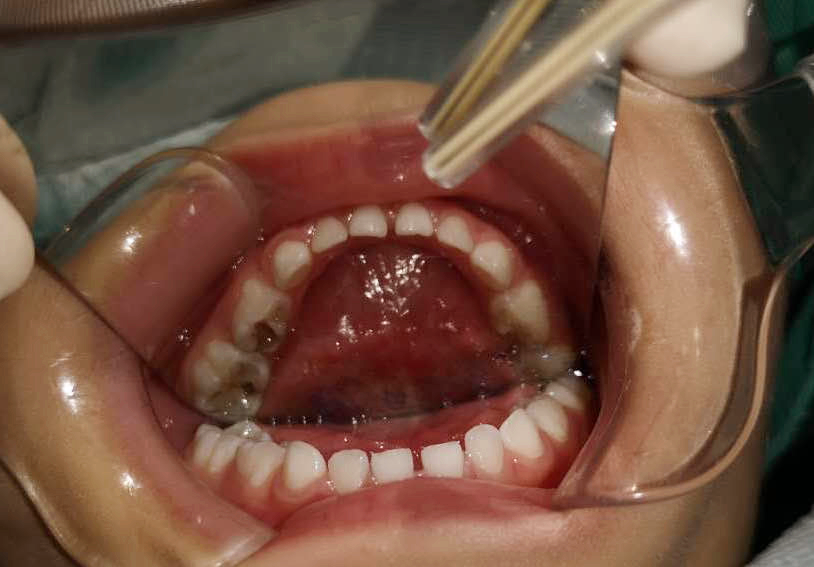

調(diào)節(jié)前

鑫鑫幾天前才接受了全麻下一次性口腔調(diào)節(jié)手術(shù),在接受手術(shù)調(diào)節(jié)之前,鑫鑫口腔內(nèi)有多顆牙齒嚴(yán)重齲壞,嚴(yán)重影響到鑫鑫的咀嚼和進(jìn)食,甚至夜間疼得無(wú)法入睡,鑫鑫的父母對(duì)此擔(dān)憂不已。

由于鑫鑫的牙齒齲壞數(shù)目多、情況嚴(yán)重,并且年齡偏小,調(diào)節(jié)難度很大,優(yōu)的調(diào)節(jié)方案是實(shí)施全麻下一次性口腔調(diào)節(jié)手術(shù)。